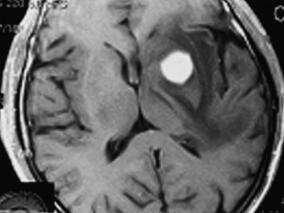

1小时条评论71岁男性,因右侧肢体无力就诊。头颅CT检查左侧基底节区可见一类圆形高密度影。活检报告显示为炎症,给予抗炎、激素治疗后,病变消失无复发。2年半后复查,头颅MRI发现右侧大脑颞叶皮质内一团块状长T1、长T2信号影。无明显主诉,给予激素治疗后,病灶明显缩小,患者...